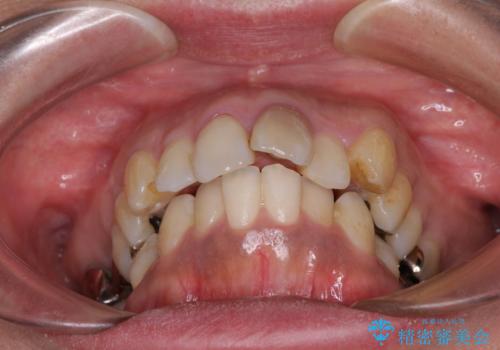

- 歯列全体が内側に倒れ込んでいることと、口元の突出感を気にして来院された患者様です。

上下ともに歯列が狭窄しており、前方に突出している状態でした。

歯が重なるような叢生も認められたため、上下左右の第一小臼歯4本を抜歯して、口元が引っ込むように治療を行うこととしました。

変色して気になっていた前歯も、オールセラミッククラウンで自然な色合いにすることができました。